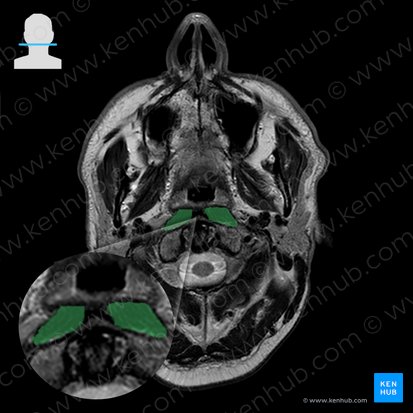

Longus capitis muscle (musculus capitis longus)

Longus capitis is a deep anterior neck muscle that runs in front of the cervical spine. Together with rectus capitis anterior, rectus capitis lateralis, longus cervicis and anterior scalene muscle, it makes the prevertebral layer of neck muscles. These muscles are wrapped up in the prevertebral layer of the cervical fascia.

Longus capitis is a long flat muscle of the anterior neck. It runs up the length of the cervical spine, adjacent to the vertebral bodies.

Longus capitis muscle originates from its inferior aspect, as four small muscle straps that run from the anterior tubercles of transverse processes of the third, fourth, fifth and sixth cervical vertebrae. From these straps, the muscle fibers run superomedially, converging into a single broad muscle belly. The muscle has one insertion on the basilar part of occipital bone, anterior to the insertion of the rectus capitis anterior muscle and lateral to the pharyngeal tubercle.

Longus capitis is the most superficial muscle of the prevertebral muscle group. Its superior aspect lies in front of the rectus capitis anterior muscle, while the inferior part slightly covers the longus cervicis muscle. The retropharyngeal lymph nodes are located on the lateral border of the longus capitis muscle. The anterior vertebral vein and the adjacent ascending cervical artery, pass through the interval between the attachments of scalenus anterior muscle and longus capitis muscle.